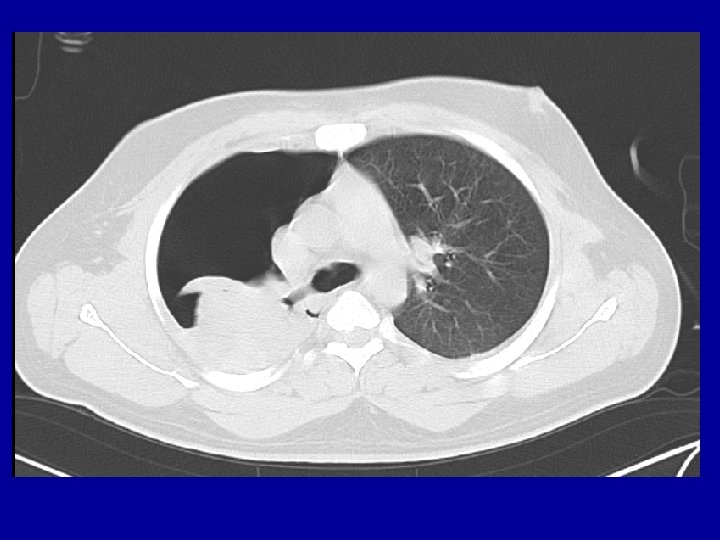

Anticipated problems needing intervention 1. 2. 3. 4. 5. Tension pneumothorax Massive Hemothorax Open Pneumothorax Flail Chest Cardiac Tamponade Treatment – Intercostal drain insertion Sealing of the wound Intubation & ventilation

Diagnose-5 places to look for • • • External Long bones Chest – x ray chest Abdomen - FAST Pelvis and Retro peritoneum Shock in a multiply injured patient is “hemorrhagic shock” unless proved otherwise

Radiology • X rays – – Chest – Pelvis – C Spine – lateral view • FAST • CT ? ? Do Not Shift Hemodynamically unstable patient to Radiology Room

CT reduces time to diagnosis CT Scanner in the Resuscitation suite